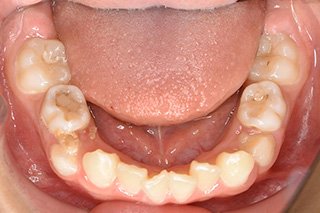

顎顔面矯正症例 11歳女児 Case

| 主訴 | 永久歯が変な所からはえてきている|顔貌 | |

|---|---|---|

| 施術内容 | 矯正1期治療 | |

| 治癒期間 | 1年5ヶ月間 | |

| 費用 | 459,200円(税込) | |

| リスク・ 副作用 | 痛みを伴う | |